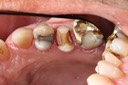

Gary Umeda #18,19,20 pre-op

Gary Umeda #18, 19, 20 prep